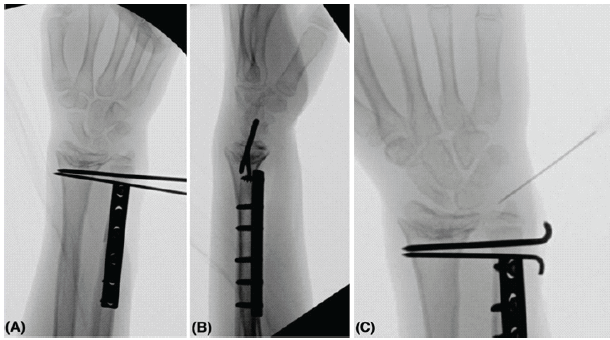

The radiographs showed bilateral symmetrical central distal radius physeal osseous bar in the background of positive ulnar variance and dorsal subluxation of the DRUJ. MRI showed evidence of stretching of the dorsal and volar radioulnar ligaments but no evidence of tears on the distal radioulnar ligament or TFCC, and a congruent distal radius joint line without arthritic changes. Due to the patient’s symptoms and deformity, the boy and parents were informed about his condition and the possible management plan for the complicated wrist joint, and they agreed to proceed with operative treatment, starting with the left wrist, which was the non-dominant but the more painful wrist joint. At 6-years and 6-months post-injury, the patient was prepared electively and underwent left side ulnar shortening osteotomy with 3.5 mm 6-holes locking compression plate fixation through direct ulnar approach, with a shortening of 1.7 cm was made as planned pre-operatively, followed by permanent distal ulnar physeal epiphyseodesis with 4.5 mm cannulated drill bit under guidance of image intensifier. The ulnar osteotomy was performed with an oscillating saw 5cm proximal to the joint line. Furthermore, intraoperatively, the patient underwent distal radioulnar joint (DRUJ) temporary fixation with two Kirschner-wires, size 2.5 mm in full supination and ulnar-to-radial fashion parallel to the joint line, followed by steroid injection of TFCC to relieve the pain (Fig. 2).

Figure 2: (a) Final intra-op left wrist anteroposterior X-ray. (b) Final intra-op left wrist lateral X-ray. (c) Intra op left wrist X-ray while doing a steroid injection of the triangular fibrocartilage complex to relieve the pain.